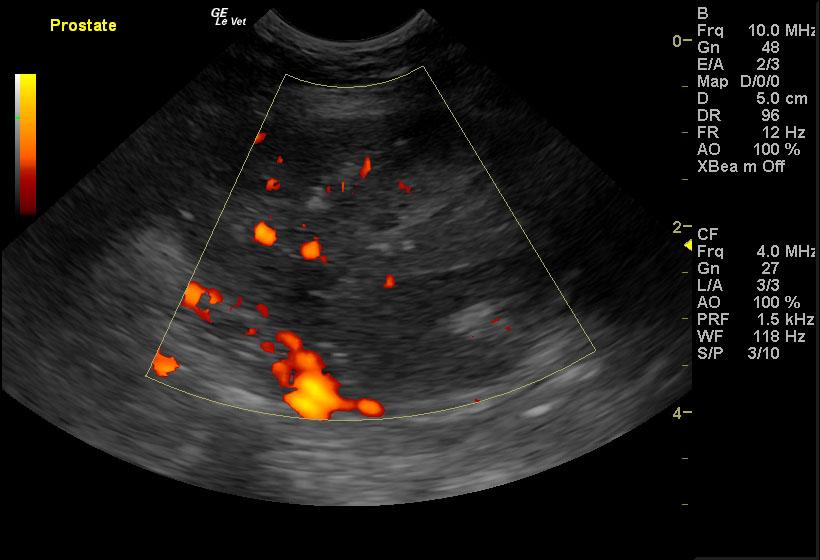

A 9-year-old NM canine mix was presented for evaluation of hematuria and urinating in the house that has not responded to a course of Baytril. Red and white blood cells were evident on urinalysis.